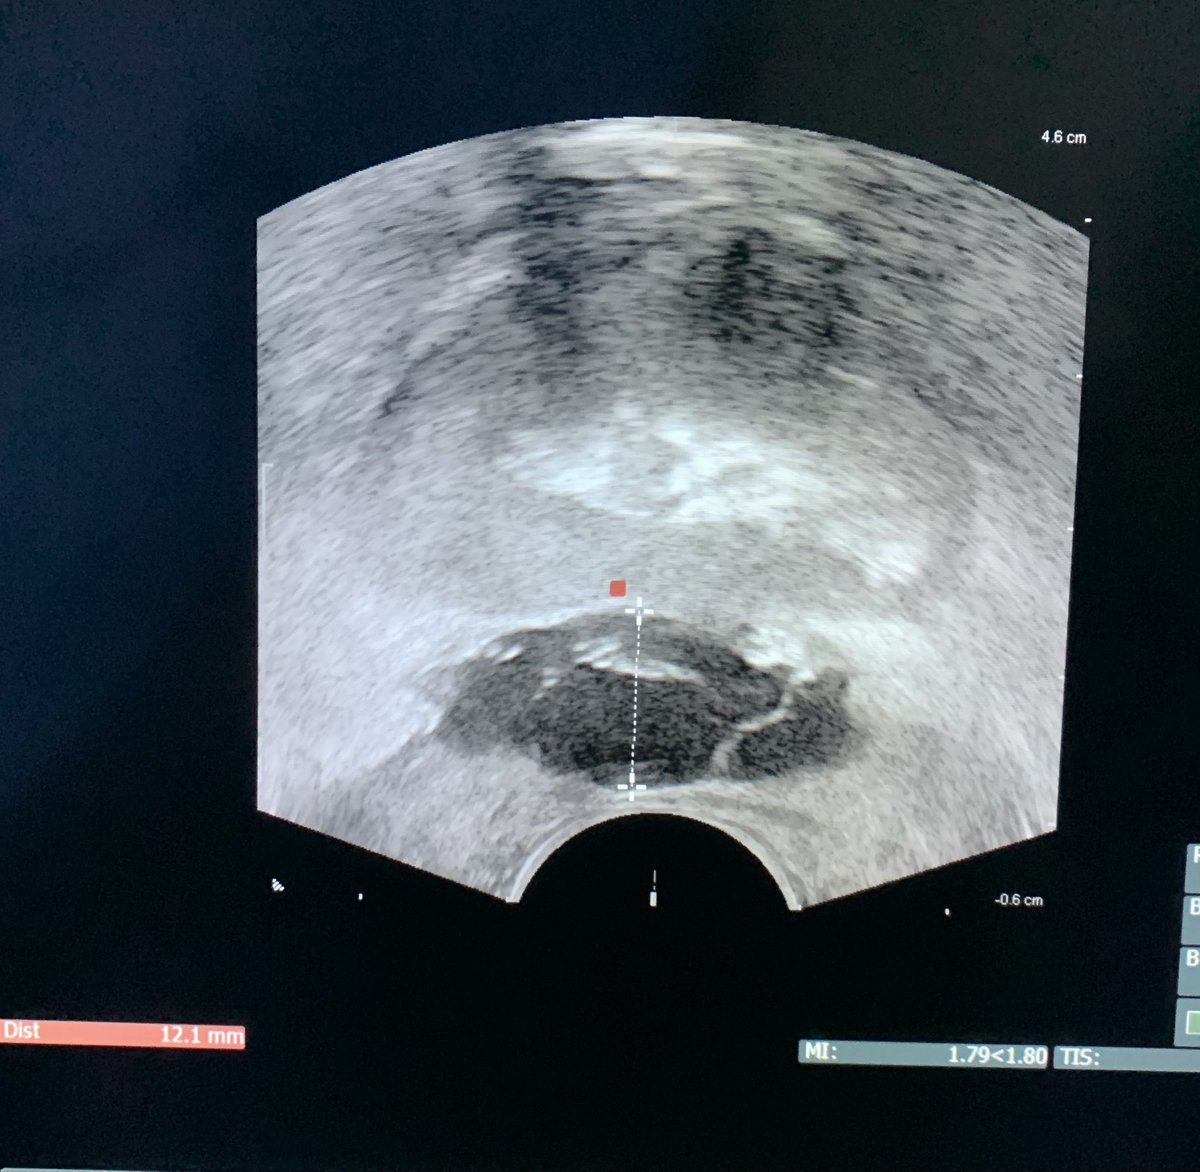

#SpaceOAR 👉🏽👉🏽 prevención de proctitis post-radiación #prostatacancer 👀 adecuada separación del recto @omarvic18 @EIvanBravoC @erenhu_gonzalez